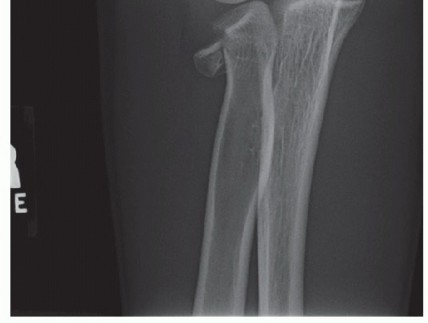

If the examination reveals wrist or forearm tenderness, the examiner should have a low threshold for obtaining bilateral wrist posteroanterior (PA) views to rule out an Essex-Lopresti lesion. Alternatively, this can be done with a one cassette view to minimize radiation exposure (FIG 9).